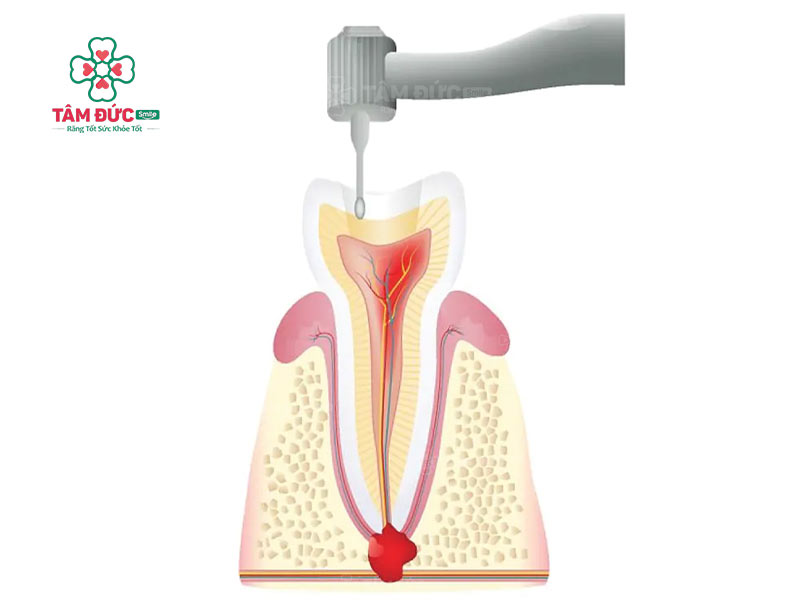

4.2. Điều trị tủy răng

Lấy tủy răng giúp loại bỏ nhiễm trùng răng bị áp xe. Bác sĩ tiến hành khoan sâu vào răng, loại bỏ mô trung tâm bị nhiễm trùng. Sau đó bác sĩ sẽ trám kín buồng tủy và ống tủy.

Đối với răng cửa, Quý khách nên bọc răng sứ để tăng độ bền và thẩm mỹ cho răng. Nếu điều trị tủy đúng cách, răng vẫn sẽ chắc khỏe mà Quý khách không cần phải nhổ răng.

Điều trị tuỷ để loại bỏ ổ vi khuẩn gây áp xe răng